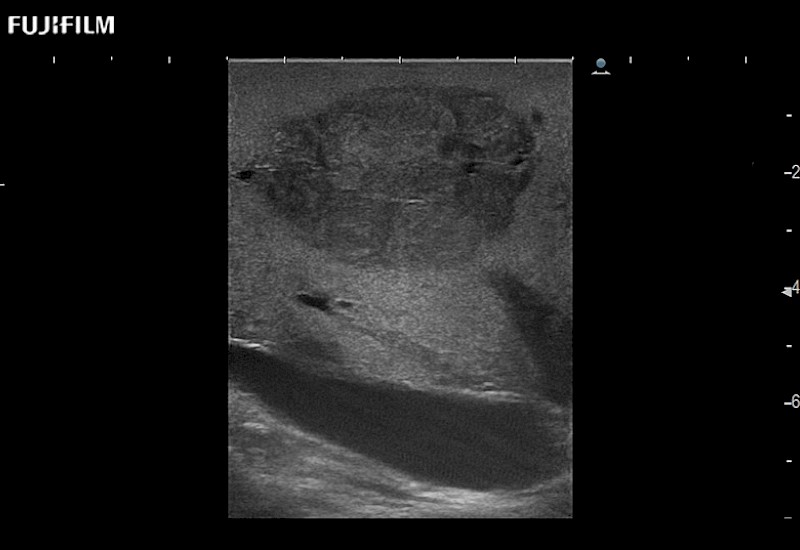

Extraordinary high-resolution digital imaging

for use during open and laparoscopic procedures: Tumor localization & staging, Ablation, Resection, Biopsy, Transplant, Abdominal exploration, Robotic surgery

- Instant feedback on tumor margin delineation

- Valuable information to guide tumor resections

- Instant feedback on tumor margin delineation

- Exceptional near and far-field resolution

- Instant feedback on tumor margin delineation

- Instant feedback on tumor margin delineation

- Instant feedback on tumor margin delineation

- Instant feedback on tumor margin delineation

- Valuable information to guide tumor resections

- Instant feedback on tumor margin delineation

- Valuable information to guide tumor resections

- Instant feedback on tumor margin delineation

- Valuable information to guide tumor resections

- Instant feedback on tumor margin delineation

- Valuable information to guide tumor resections

- Instant feedback on tumor margin delineation